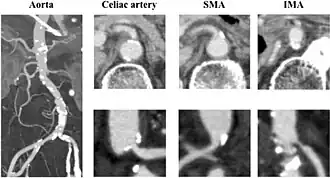

CT angiogram demonstrating stenosis of the superior mesenteric artery. | |

Abdominal angina is diagnosed by identifying stenosis with imaging.[10] Since the symptoms of abdominal angina overlap with various other disorders, other causes of symptoms are ruled out as a part of the diagnostic process. Gastric ulcers, abdominal aortic aneurysms, and gastrointestinal cancers can have similar symptoms and can be ruled out by esophagogastroduodenoscopy, CT scans, or MR angiogram. Other differential diagnoses include GERD, dietary or food sensitivities, constipation, pancreatitis, abdominal abscess, appendicitis, irritable bowel syndrome, gastroenteritis, hepatitis, and inflammation of the gastrointestinal system.[11] Duplex ultrasound, MR angiography, angiography, and computed tomography angiography can be used to help confirm the diagnosis of abdominal angina.[3] Duplex ultrasound may be used to screen for abdominal angina but is not ideal for visualizing stenosis. Angiography, MR angiography, or CT angiography can be used to further visualize the celiac and mesenteric arteries.[12]